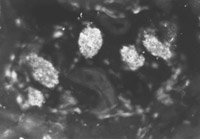

用特異的小鼠抗人角蛋白19型的單克隆抗體(McAb)對正常和燒傷皮膚免疫細(xì)胞化學(xué)觀察結(jié)果表明,兩例正常皮膚表皮再生干細(xì)胞數(shù)量較少,可見少量顯示熒光的表皮細(xì)胞再生干細(xì)胞(圖5-4-1),即角蛋白19型陽性細(xì)胞。燒傷后24h,熒光顯微鏡下,顯示熒光的表皮再生干細(xì)胞數(shù)量中等程度(圖5-4-2),燒傷后4天,在汗腺、毛細(xì)血管和毛囊周圍可見開始增多的潛在表皮干細(xì)胞(圖5-4-3)。

燒傷后7天(圖5-4-4),燒傷后14天(圖5-4-5),在該兩時間點(diǎn)鏡下可見比燒傷后4天繼續(xù)增多的表皮再生干細(xì)胞。潛在的再生干細(xì)胞即含人角蛋白19型細(xì)胞的數(shù)量達(dá)到燒傷療程中的峰值(數(shù)量最多)。至燒傷后21天(圖5-4-6)和28天(圖5-4-7)兩時間點(diǎn)潛在再生干細(xì)胞數(shù)量又減至一定的水平。觀察中發(fā)現(xiàn)患者經(jīng)濕性燒傷醫(yī)療技術(shù)治療后,潛在再生干細(xì)胞的增生狀態(tài)有一定的變化規(guī)律。潛在再生干細(xì)胞可能是表皮再生的干細(xì)胞的來源,這些在熒光顯微鏡下顯示熒光的細(xì)胞是深Ⅱ度和淺Ⅲ度燒傷后還存在的潛在的表皮再生干細(xì)胞。這些細(xì)胞可使燒傷濕性醫(yī)療技術(shù)治療的深Ⅱ度燒傷無瘢痕愈合,淺Ⅲ度燒傷皮膚再生。

圖5-4-1 正常皮膚、未見角蛋白19型陽性細(xì)胞  ×200

圖5-4-2 經(jīng)MEBT/MEBO治療燒傷后 24h,可見中等程度蛋白19型陽性細(xì)胞   ×200

圖5-4-3經(jīng)MEBT/MEBO治療燒傷后4天,角蛋白19型陽性細(xì)胞增多  ×200

圖5-4-4 經(jīng)MEBT/MEBO治療,燒傷后7天,角蛋白19型陽性細(xì)胞數(shù)量達(dá)峰值  ×200

圖5-4-5 經(jīng)MEBT/MEBO治療,燒傷后14天,角質(zhì)蛋白19型陽性細(xì)胞數(shù)量達(dá)峰值  ×200

圖5-4-6 經(jīng)MEBT/MEBO治療,燒傷后21天,角蛋白19型陽性細(xì)胞減少  ×200

圖5-4-7 經(jīng)MEBT/MEBO治療,燒傷后28天,角蛋白19型陽性細(xì)胞減少  ×200

圖5-4-1圖5-4-7均為應(yīng)用小鼠抗人角蛋白19型單克隆抗體于冰凍切片染色(生物素-抗生物素蛋白DSC體系間接免疫熒光)照片。